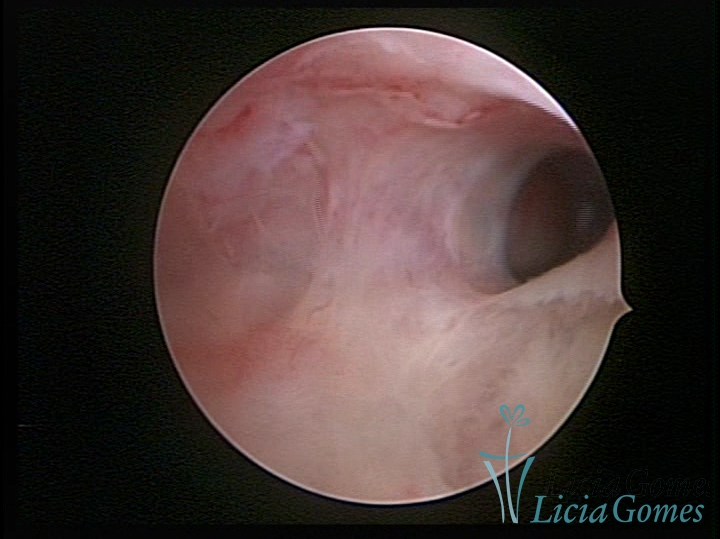

• SINÉQUIA TIPO FIBROMUSCULAR